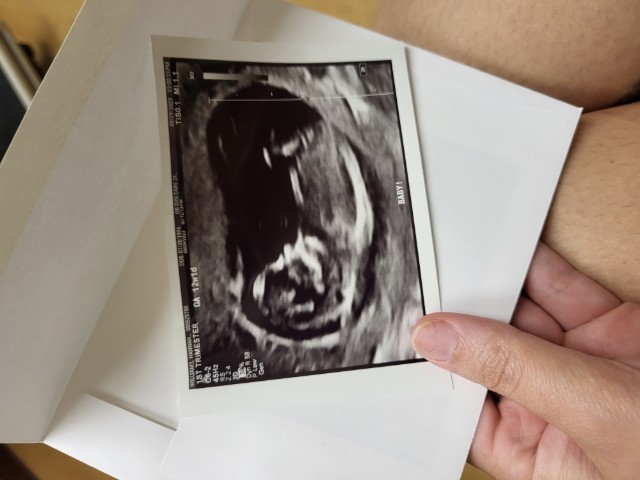

Its a girl!

Im in tears of joy, our blood test came back and its a girl! Due March 11!